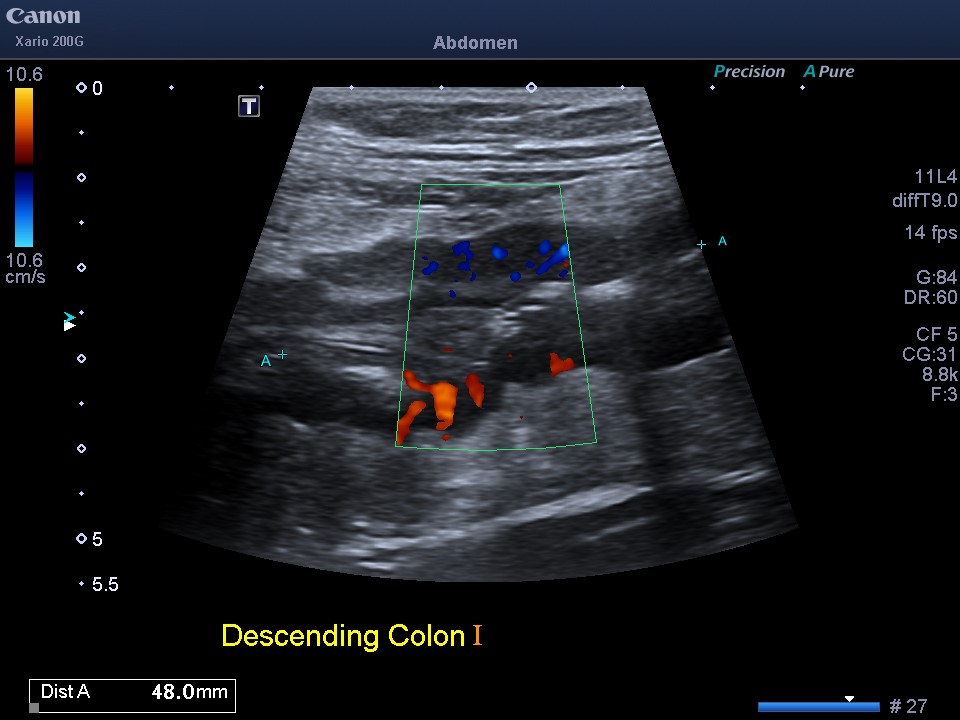

36F w stricturing colonic and perianal Crohns presents 13/40 gestation with abdominal pain and constipation; had self-ceased ustekinumab - improved with IV steroids and restarting ustekinumab, normal foetal scan. What did the IUS show?